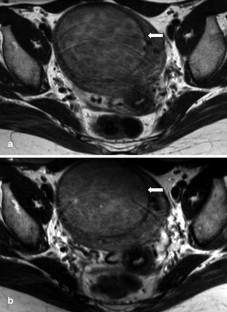

The purpose of this study was to evaluate if 3.0 T allows for clinically useful pelvic magnetic resonance imaging, i.e. if familiar image quality and tissue contrast can be achieved at 3.0 T as compared with at 1.5 T. Adapting a 1.5-T protocol to the 3.0-T environment is subject to a variety of factors. In order to reduce the number of potential variables, we chose two cornerstones: the 3.0-T sequence should have similar spatial resolution and acquisition time; furthermore, the contrast parameters repetition time (TR) and echo time (TE) were kept identical. Based on this modified 3.0-T T2-weighted turbo spin-echo sequence (TR/TE 2,705/80 ms; 0.7×1.04×4 mm measured voxel size; field of view 360 mm; 4.03-min scan time) we performed an intraindividual study on 19 patients with the 1.5-T sequence as the standard of reference. Two radiologists analyzed the examinations in consensus with regard to tissue contrast (visualization of zonal anatomy of the uterus and/or delineation of pathologic findings) rated on a three-point scale (3 is 3.0 T better; 2 is 3.0 T equal; 1 is 3.0 T worse than 1.5 T). In addition, the signal difference between muscle and bone marrow was measured as a marker for tissue contrast. The analysis of the image quality comprised the level of the artifacts (rated on a five-point scale: 1 is no artifacts; 5 is nondiagnostic study), the visual signal-to-noise ratio (rated on a three-point scale) and detail delineation. Only minor artifacts were observed at both 1.5 and 3.0 T; the difference was not statistically significant. The visual signal-to-noise ratio and the delineation of image details were rated equal for 1.5 and 3.0 T. With regard to image contrast, both qualitative analysis as well as quantitative analysis revealed comparable image contrast for the 1.5- and 3.0-T protocols. Pathological findings were seen equally well with both field strengths. Clinically diagnostic pelvic studies of high image quality can be obtained using a 3.0-T scanner with our modified examination protocol. To fully exploit the capability of the high-field technique, and to point out potential advantages, further intraindividual studies are needed, with the adjustment of other imaging parameters to the high-field environment.

Fig. 2